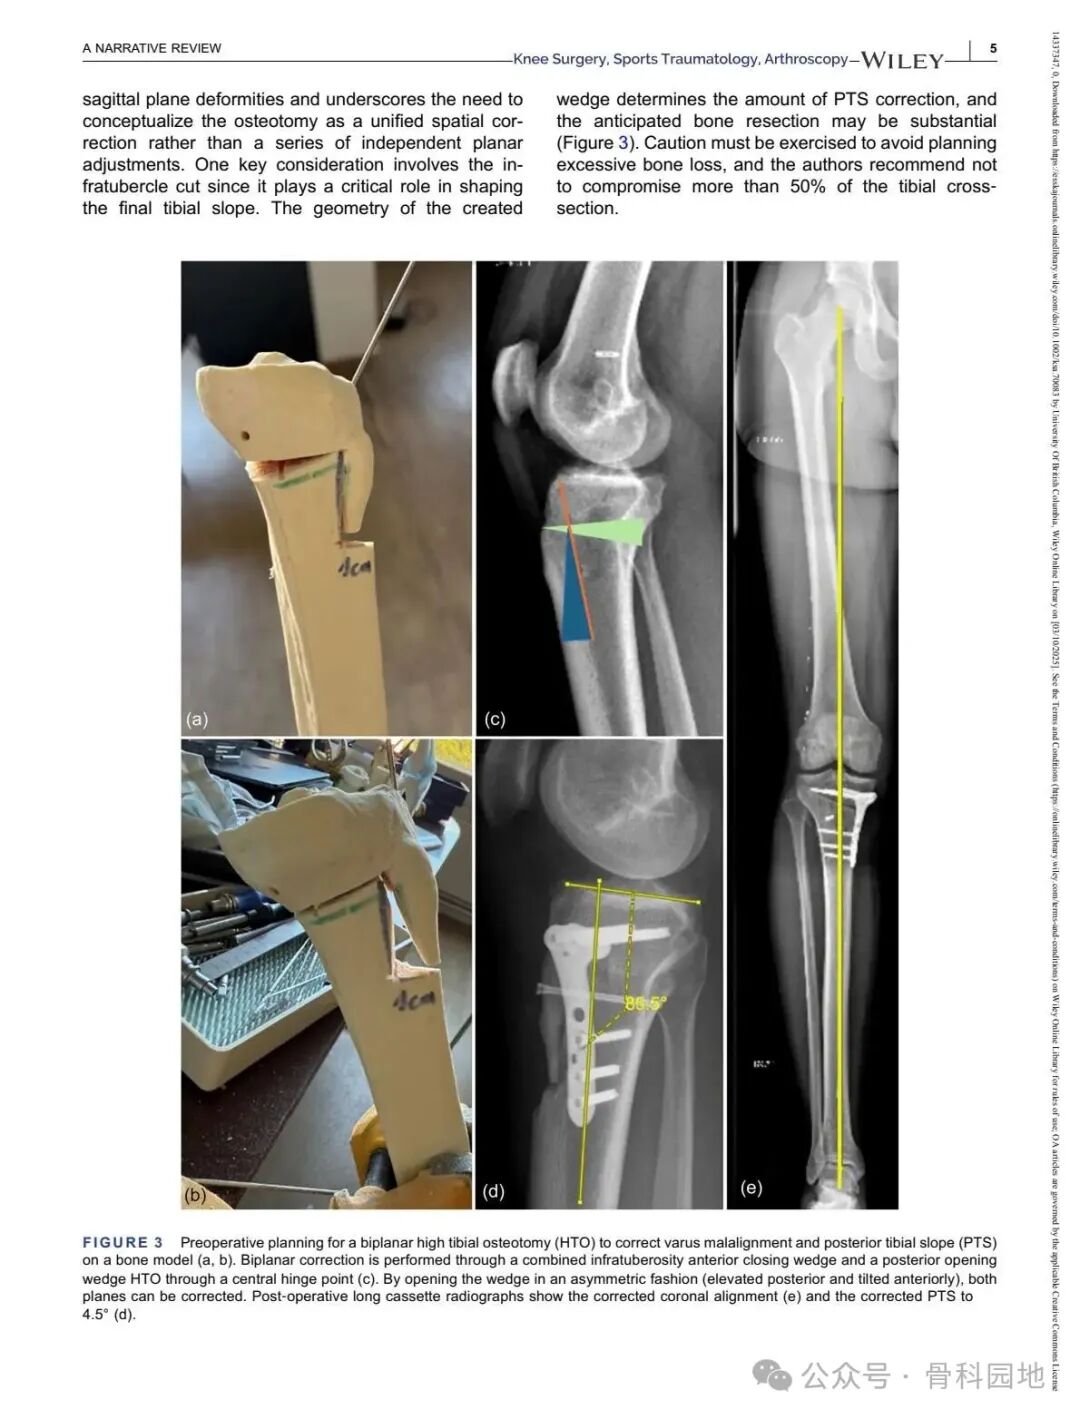

Although conventional high tibial osteotomy (HTO) primarily addresses coronal plane malalignment, the importance of sagittal plane alignment—specifically the posterior tibial slope (PTS)—cannot be overlooked in the setting of cruciate ligament insufficiency. Combined coronal and sagittal plane deformities are relatively rare and present unique surgical challenges. This narrative review summarizes the available literature and presents technical tips for managing complex biplanar deformities through a case‑based discussion of different techniques.